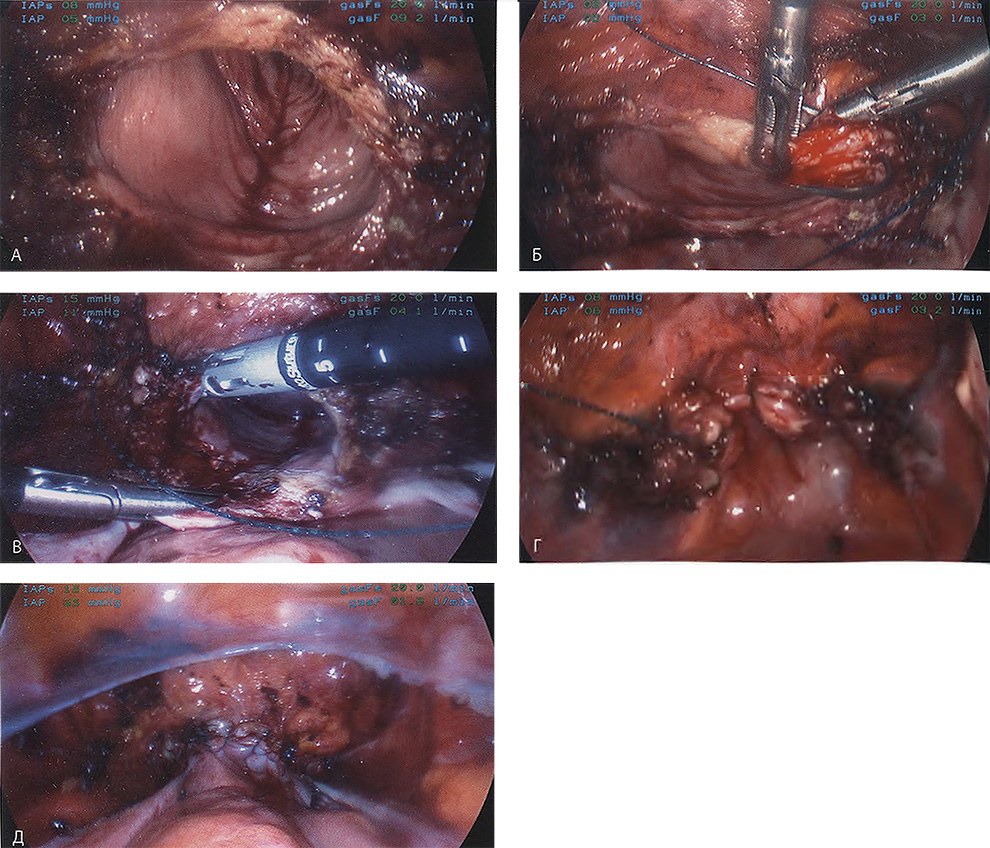

Коагулируют и пересекают так называемые поддерживающие связки матки (рис. 12-44 Г, Д). Возможно, потребуется разделить ткани, соединяющие мочевой пузырь с передней стенкой влагалища. После этого вскрывают влагалище и коагулируют все кровоточащие сосуды. Если хирург владеет методами лапароскопического наложения швов, то он зашивает культю влагалища. Предварительно матку извлекают через влагалище или путём морцелляции (рис. 12-45 и 12-46).

Рис. 12-46. А. Видно вскрытое влагалище; обратите внимание на переднюю стенку влагалищной манжетки. Б. Культю влагалища зашита наглухо. В. Игла проведена через переднюю и заднюю стенки культи влагалища. Г. Культя влагалища зашита наглухо. Д. Завершение зашивания культи влагалища